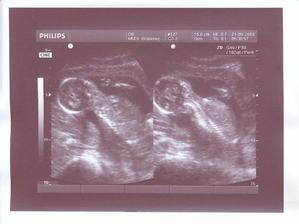

11.6. velký UTZ v Gennetu dopadl na výbornou! Kromě všech příjemných zpráv o super vývoji naše miminka, jsme se dozvěděli, že čekáme chlapečka!!!!!!! 🙂 Taťka jako první poznal pytlík, maminka až o trochu později 🙂 Máme obrouvskou radost, že je Hoňánek naprosto v pořádku a už nám váží 404gramů 🙂